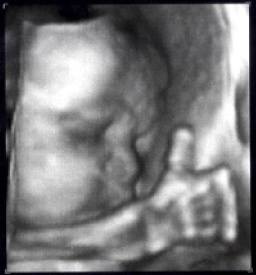

超音波検査も3D機能でおなかの赤ちゃんの様子がよりわかるようになりました。USBを持参されると超音波検査の画像をご自宅でご家族と一緒に見ることができます。